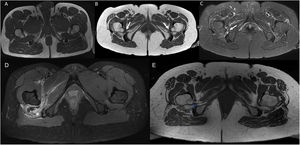

La resonancia magnética (RM) de cadera es la prueba de referencia para observar la disminución del espacio isquiofemoral12 (fig. 1). Se considera la existencia de pinzamiento cuando el espacio isquiofemoral es menor de 23 (±8) cm, o bien cuando la anchura del músculo cuadrado femoral es menor de 12 (±4) cm5,8. No obstante, existe controversia con el uso de estos valores de referencia1,11, dado que este espacio es muy variable según el ciclo de la marcha y la posición del paciente durante la prueba de imagen, y además la RM suele sobreestimar su medida, por lo que la exploración física del paciente resulta fundamental en el diagnóstico de esta patología. Con la RM también se puede objetivar alteración de señal del músculo cuadrado femoral por edema o rotura de fibras, infiltración grasa en casos de pinzamientos crónicos, o tendinopatía insercional de isquiotibiales o iliopsoas2,9,11. Otra técnica que resulta muy útil es la ecografía dinámica de cadera para corroborar el pinzamiento del espacio isquiofemoral con el cambio de posición del miembro inferior, así como valorar si la clínica del paciente es debida a pinzamiento o a otras causas11.

Composición de imágenes RM en el plano axial. Secuencias potenciadas en T1 (A y B) y STIR (C). A)Imagen de anatomía normal. B)Paciente número 2 de nuestra serie: disminución bilateral del espacio isquiofemoral (flechas blancas). C)El mismo paciente, donde además se aprecia leve edema en las partes blandas (cuadrado femoral) del espacio isquiofemoral derecho y atrofia de ambos. D)Imagen de RM en plano axial. Secuencia potenciada en densidad protónica (DP) con saturación grasa. Engrosamiento con edema y hematoma en músculo cuadrado femoral derecho (*) por rotura en paciente con pinzamiento del espacio isquiofemoral. E)Imagen RM en plano axial. Secuencia potenciada en T1. Medición del espacio cuadrado femoral e isquiofemoral en paciente con pinzamiento.